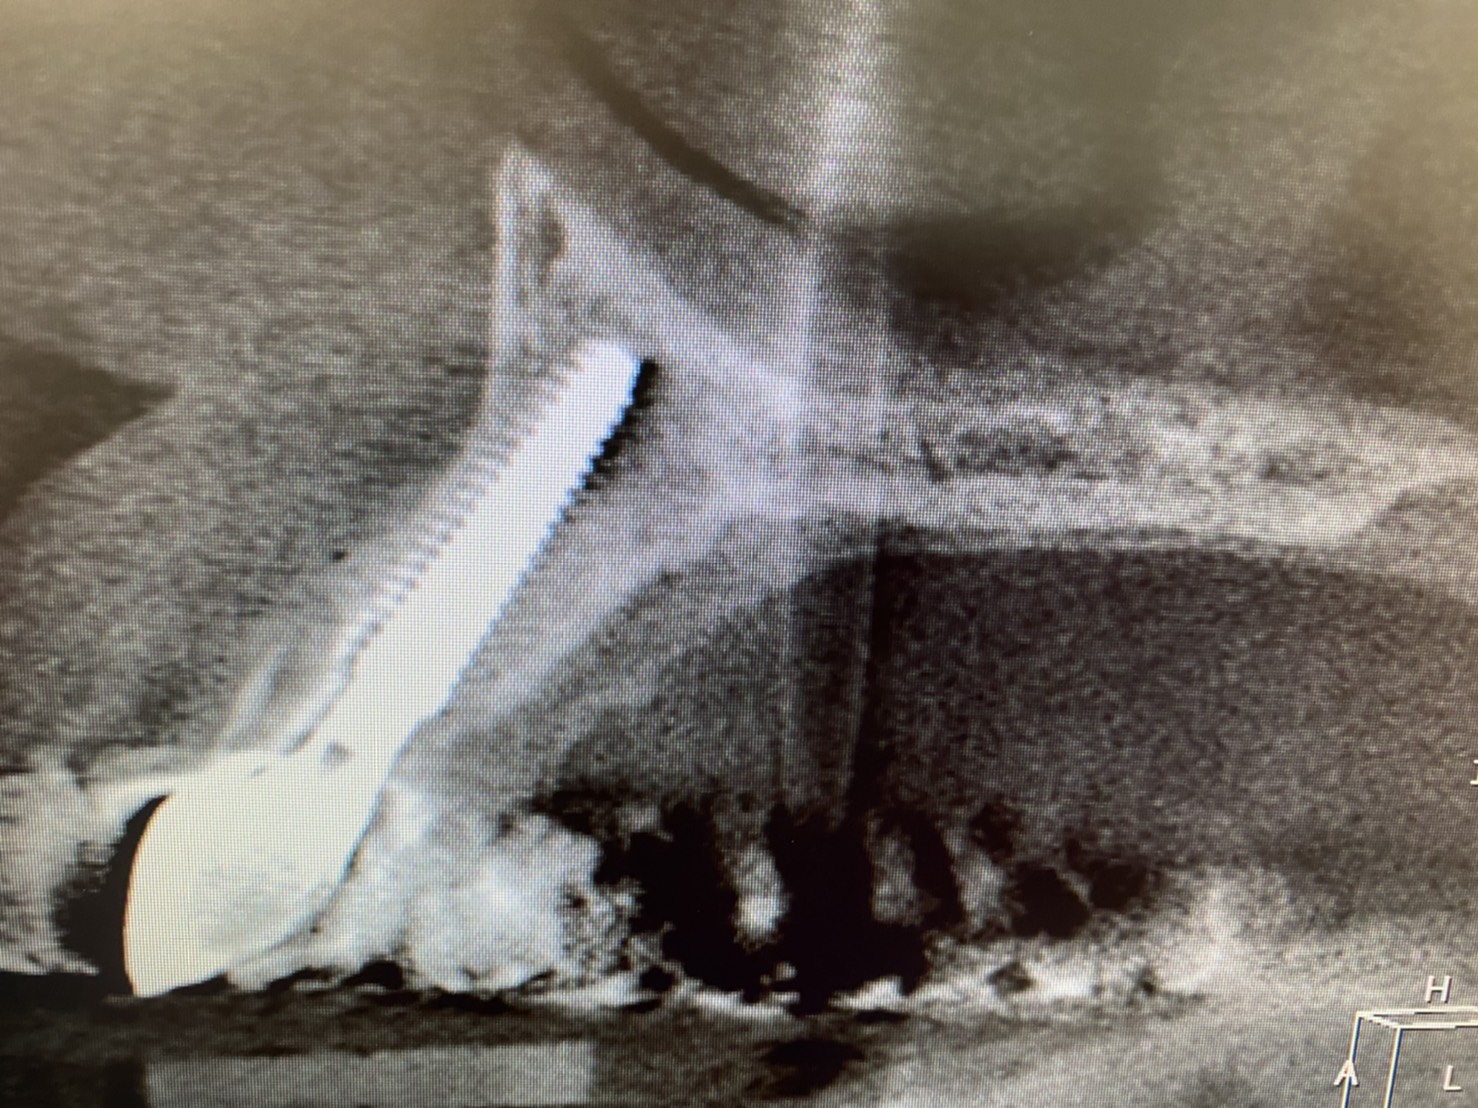

本日は須田理事長による前歯インプラントの最終補綴物セットがありました。

昨年12月初旬にオペした方です

ルートメンブレン(頬側一部の歯根を意図的に残す方法)を行ったオペでした。

審美エリアですので、少しでも、骨の吸収を招かない、更には歯肉の退縮をさせない為に

傾斜埋入にならないように、アップライトな角度でドリリングし、低位舌側に位置させると、自ずと、画像の紫色ラインのような通称SプロファイルやらLプロファイルと呼ばれる形態に作りあがります